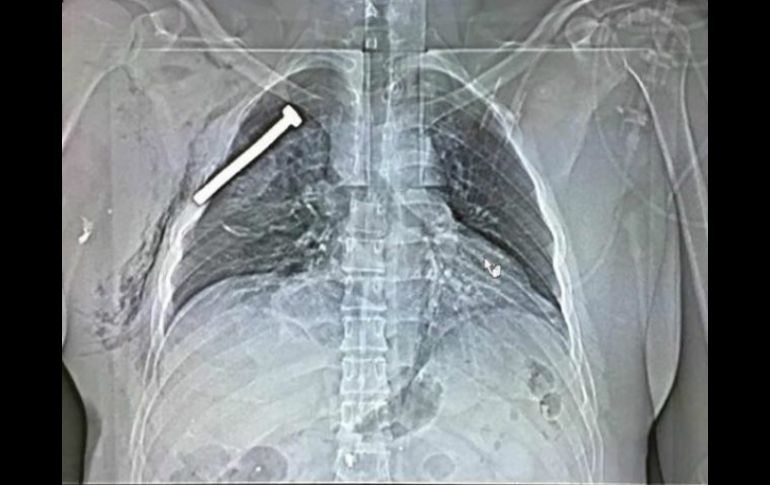

Imagen de una radiografía de una de las víctimas de los atentados de Bruselas, con un tornillo incrustado en el pecho. EFE / Stringer